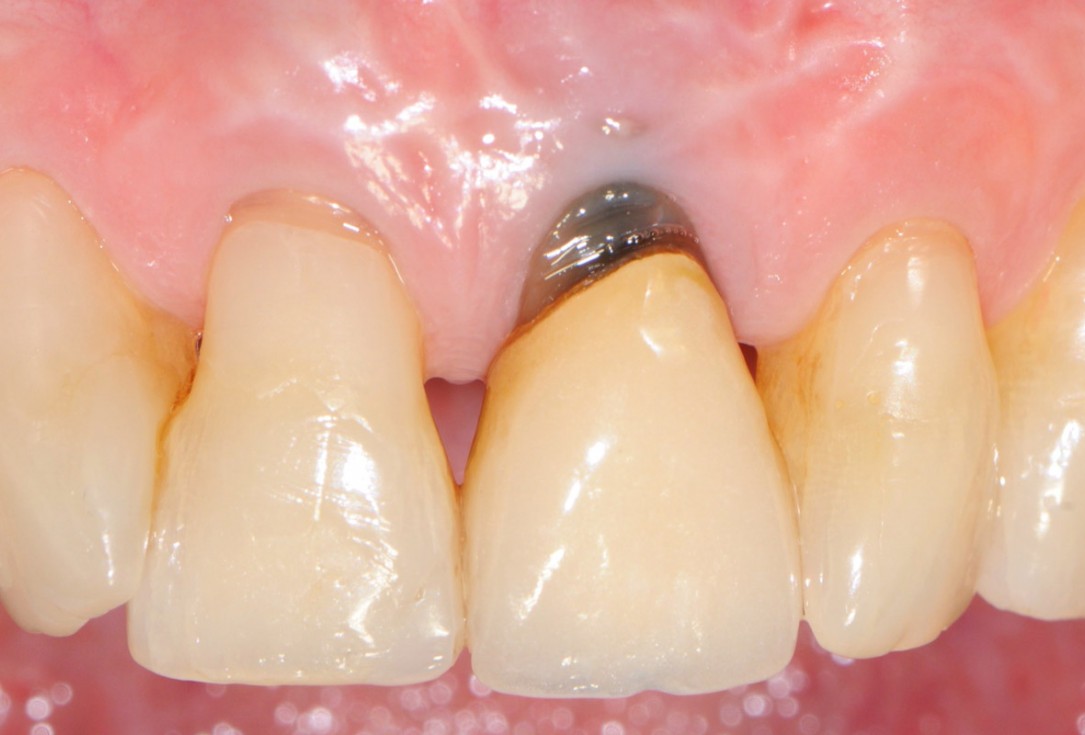

1/18 - Initial clinical situation showing strongly compromised tooth 21Tooth extraction and socket sealing with mucoderm® - Dr. A. Rossi

Initial clinical situation showing strongly compromised tooth 21